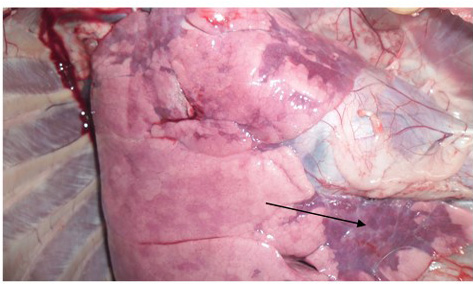

Congested and consolidated pneumonic lung with dark red discoloration (arrow)

Congestion and consolidation of cardiac lobe of lung (Arrow)